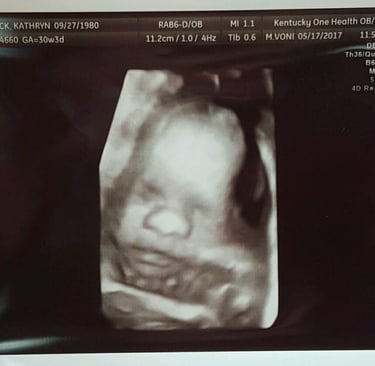

"There is no heartbeat." A statement that changed my life forever. For the first several months, I was crushed. It was isolating and I felt like a failure. BUT, that little heartbeat that once was gave me so much enlightenment. Avery's heartbeat was beautiful to hear as all my babies' heartbeats once did. The heartbeat during a pregnancy is a sound of joy, happiness and hope! Although my sweet Avery's heart stopped too soon, she had a purpose and made me a better person.

Our sweet Avery’s existence strengthened my faith. She made me more grateful. I see her in my boys and can't wait til we are all together one day in Heaven. As we approach Avery's 8th birthday this year, I thank God every day for blessing me with her little brothers and trusting me with their precious lives. What a gift a baby is! And I am proudly honored to be a mother of an angel who has helped me become the woman and mother I am today.